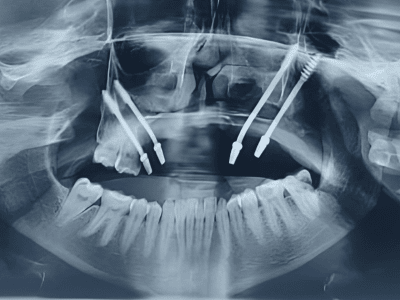

Periodontics, Dental Implants, and Advanced Gum Care. With a BDS and MDS in Periodontics, she

provides expert treatment for gum diseases, receding gums, and dental implant procedures using the

high standards of hygiene and comfort. Her expertise includes laser dentistry, cosmetic smile

From routine checkups to complex gum treatments, dental implants, laser dentistry, root canal treatments (RCT), and smile

We use advanced dental equipment, including laser dentistry, digital X-rays, and minimally invasive techniques, ensuring precision, safety

Dr. Bhardwaj specializes in Periodontics, offering treatments for gum diseases, dental implants, laser dentistry, root canal treatments (RCT), teeth whitening, smile makeovers, and general dental care.